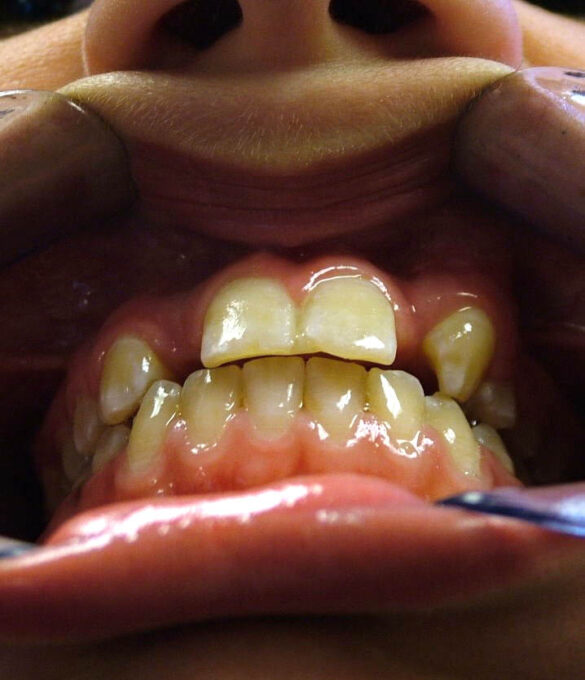

La momentul prezentării în clinică, în decembrie 2002, pacienta avea 8 ani şi o lună şi suferea de fibroză chistică şi de o deficienţă de dezvoltare a etajului mijlociu al feţei. Aceasta prezenta o anomalie de clasa I care mima o anomalie de clasa a III-a. Incisivii centrali, laterali şi caninii temporari maxilari, precum şi molarii prim şi secund de pe partea stângă erau în ocluzie inversă. În plus, pacienta prezenta coloraţii ale dinţilor de etiologie idiopatică (fig. 1). Autorii au considerat coloraţiile ca fiind de suprafaţă, extrinsece şi nu determinate de fibroza chistică, dovadă îndepărtarea acestora prin periaj profesional. Radiografia panoramică efectuată cu 6 luni înainte de prezentarea în clinica stomatologică relevă anodonţia incisivilor laterali superiori şi a premolarului secund drept inferior, ca şi posibila incluzie a caninilor maxilari, în special a celui stâng (fig. 2).